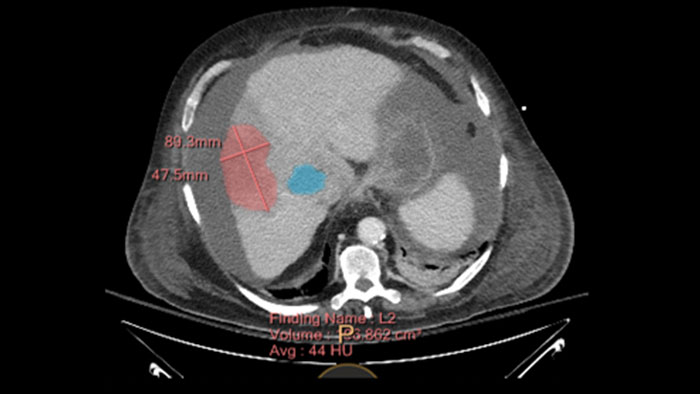

Tumor Tracking qEASL

Multi Modality Tumor Tracking qEASL (MMTT qEASL)

Semi-automatic tumor quantification

This semi-automated 3D (Volumetric) tumor response assessment tool, based on EASL (European Association for the Study of the Liver) criteria incorporates functional information from contrast-enhanced scans.

• Multi Modality Tumor Tracking supports the creation of Quantitative EASL (qEASL) maps used to measure segmented volumes of interest (VOI) in heterogeneous lesions.

• Data are presented as color map overlaid on the scans to show regional tumor enhancement heterogeneity. The color regions of the segmented lesions are where there is more enhancement than the pre-defined reference region.